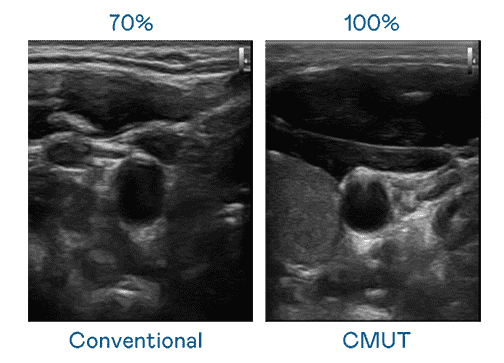

CMUT 技术是一种用电容式微机电元件来产生超音波讯号的技术。。与传统 PZT 压电式技术相比,,CMUT 频宽增加 30%,,更宽频的超音波讯号让影像解析度大幅提升,,是实现高影像品质医疗超音波扫描、、促进精准医疗发展的关键技术。。。

大频宽带来超清晰影像

超音波影像的解析度高低,,,,首先取决于探头能发出的讯号频宽。。。。z6mg·人生就是博 CMUT 可提供高清晰的超音波讯号,,提供高频宽、、、、高灵敏度、、影像纹理细节更高的超音波影像,,协助医护人员缩短影像判读时间及利用精准的医疗影像进行诊断。。